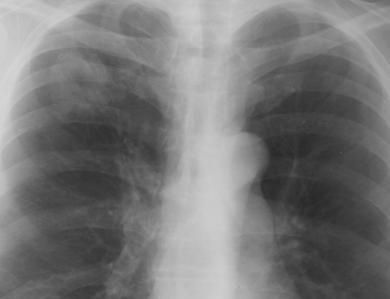

Fig. 23 – Cancer hilar stang (opacitate proximala intensa, ovalara, difuz delimitata, cu prelungiri periferice)

Cancerul bronhiilor mici / bronhiolo-alveolar – se caracterizeaza radiologic prin:

Opacitate distala rotunda (coin lesion) sau ovalara, situata in plin parenchim pulmonar, de dimensiuni diferite, densitate mica, cu contur neregulat, policiclic, ce deplaseaza si infiltreaza scizurile;

adenopatie hilara satelita care, impreuna cu tumora, realizeaza un aspect bipolar, “in haltera”

revarsate pleurale ce se refac rapid dupa evacuare;